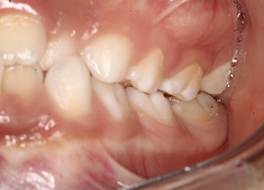

Análisis intraoral: Al observar la boca del paciente nos encontramos que la mucosa está húmeda y lubricada con pigmentación melánica, el frenillo es de inserción mucosa; hay poca inflamación de las encías. El paladar duro es profundo. El paciente está en dentición mixta, existe una mordida cruzada anterior con apiñamiento en el sector anteroinferior. En el arco superior se observa un diastema entre los incisivos centrales superiores permanentes, también se observa que estos dientes están ligeramente rotados. La relación molar de ambos lados es de clase III y la relación de los caninos deciduos también es de clase III.

Fig.3 Fotografía intraoral de frente Fig.

4 Fotografía intraoral de 45°

Fig. 5 Fotografía intraoral lado derecho Fig. 6 Fotografía intraoral lado izquierdo